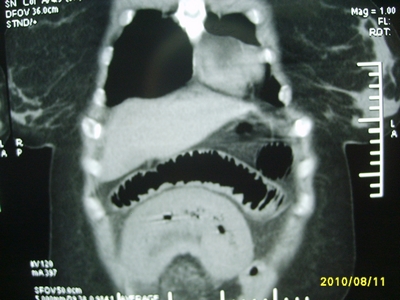

5天前突发腹痛剧烈难忍,伴解淡血水样便。近一天来腹痛缓解,没有明显的腹膜炎的体征。今天照的腹部ct。从ct上看感觉是一个绞窄性肠梗阻,但是现在没有腹痛。不好解释

请放射科的专家,帮帮看看。从影像学的角度来看看。这是不是一个绞窄性肠梗阻。

要有麻烦了,感觉小肠有套叠还有扭转改变,估计部分已有坏死。

高位肠梗阻(不全性),原因小肠(空肠)扭转,肠壁水肿增厚,成年人肠梗阻要排除合并占位,建议手术。

绞窄性肠梗阻_肠管套叠 扭转,肠壁明显水肿。

支持绞窄性肠梗阻,肠壁明显水肿并见有多发小泡状积气--肠坏死

考虑绞窄性肠梗阻并肠坏死。